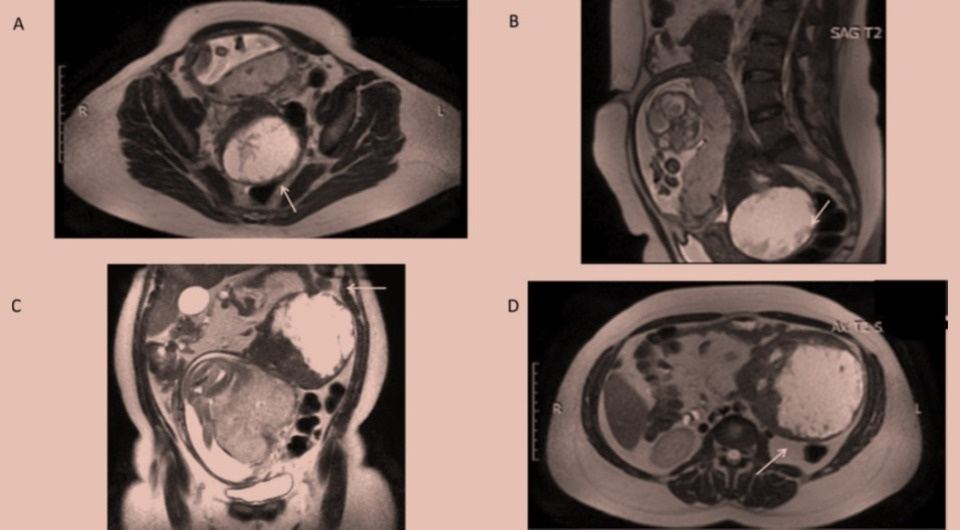

Итальянские хирурги обнаружили две крупные лейомиомы матки у пациентки на 21 неделе беременности. Одна из них располагалась под диафрагмой и мешала женщине дышать, а вторая занимала Дугласово пространство, что могло привести к нарушениям во время родов. Верхнюю опухоль вырезали, а нижнюю оставили из-за высоких акушерских рисков. Здоровый ребенок родился в срок с помощью кесарева сечения. Случай описан в BMJ Case Reports.

Диагностика и лечение объемных образований в брюшной полости значительно ограничены во время беременности. Для визуализации этой области доступны только ультразвуковые исследования и магнитно-резонансная томография, при этом анализы крови на опухолевые маркеры могут быть неинформативны. Хирургическое лечение таких опухолей представляет большой риск как для матери, так и для плода, однако и выжидательная тактика может привести к патологиям беременности и родов.